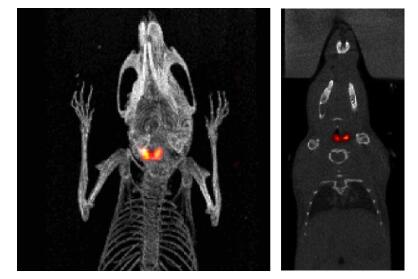

圖 8. 來(lái)自肺腫瘤模型研究的小鼠的 PET(左)和 PET/CT( 右) 圖像, 6.47MBq( 175μ Ci)

[18F]FDG, 15min PET【1】 【2】 。